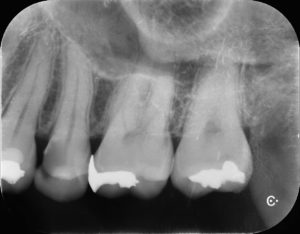

左上小臼歯部に歯髄に近接した深在性のう蝕をみとめる。痛み等の症状はないため歯髄の保存を試みることとした。

ラバーダム防湿を行い、唾液からの保護を行った後、う蝕を除去していくと容易に歯髄が露出した。炎症性の冠部歯髄を除去し、マイクロスコープ強拡大下で断髄面の状態を確認したところ正常な血管の走行を認めたため、MTAセメントを用いて歯髄保護を行った。